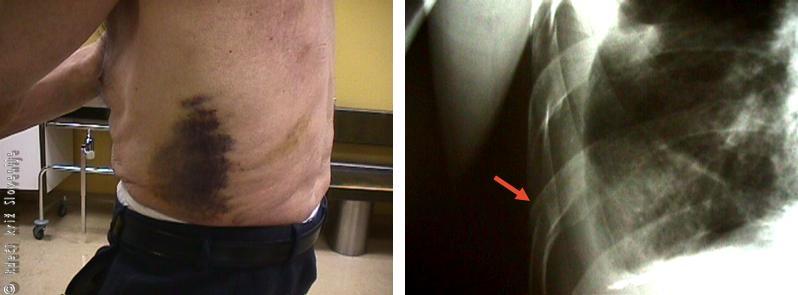

Slika 2

Udarnina ali kontuzijska značka je najbolj izražena na tistih delih telesa, kjer je koža tanka, raztegljiva (koža veke in mošnje).

Pogosto se na mestu udarca pojavi oteklina, ki je odvisna od zgradbe poškodovanega tkiva (največja je v področju mošnje in vek, kjer je koža zelo raztegljiva in tanka). Barva kontuzijske značke – modrice se spremeni od obrobja (periferije) proti osrednjemu delu v zeleno (5–7 dni), v rumeno (7–10 dni), v rjavo (10–14 dni) in v 2–4 tednih je koža na udarjenem mestu normalne barve.

Pri manjših udarninah koža ni prekinjena, večje pa pogosto spremlja razpočna rana neostrih robov, največkrat kot posledica padcev in topih udarcev z različnimi predmeti ali s pestjo. Udarnine v predel prsnega koša pogosto spremljajo zlomi reber, v prometnih nezgodah tudi zlomi prsnice. V teh primerih moramo pomisliti tudi na poškodbo pljuč in srca. Pri močnih udarninah lahko počijo jetra, vranica ali ledvice, kar lahko povzroči takojšnje ali kasne hude krvavitve.

Slika 3

Pri udarninah v področje prsnega koša moramo pomisliti tudi na poškodbo skeleta, zlasti na zlom reber.